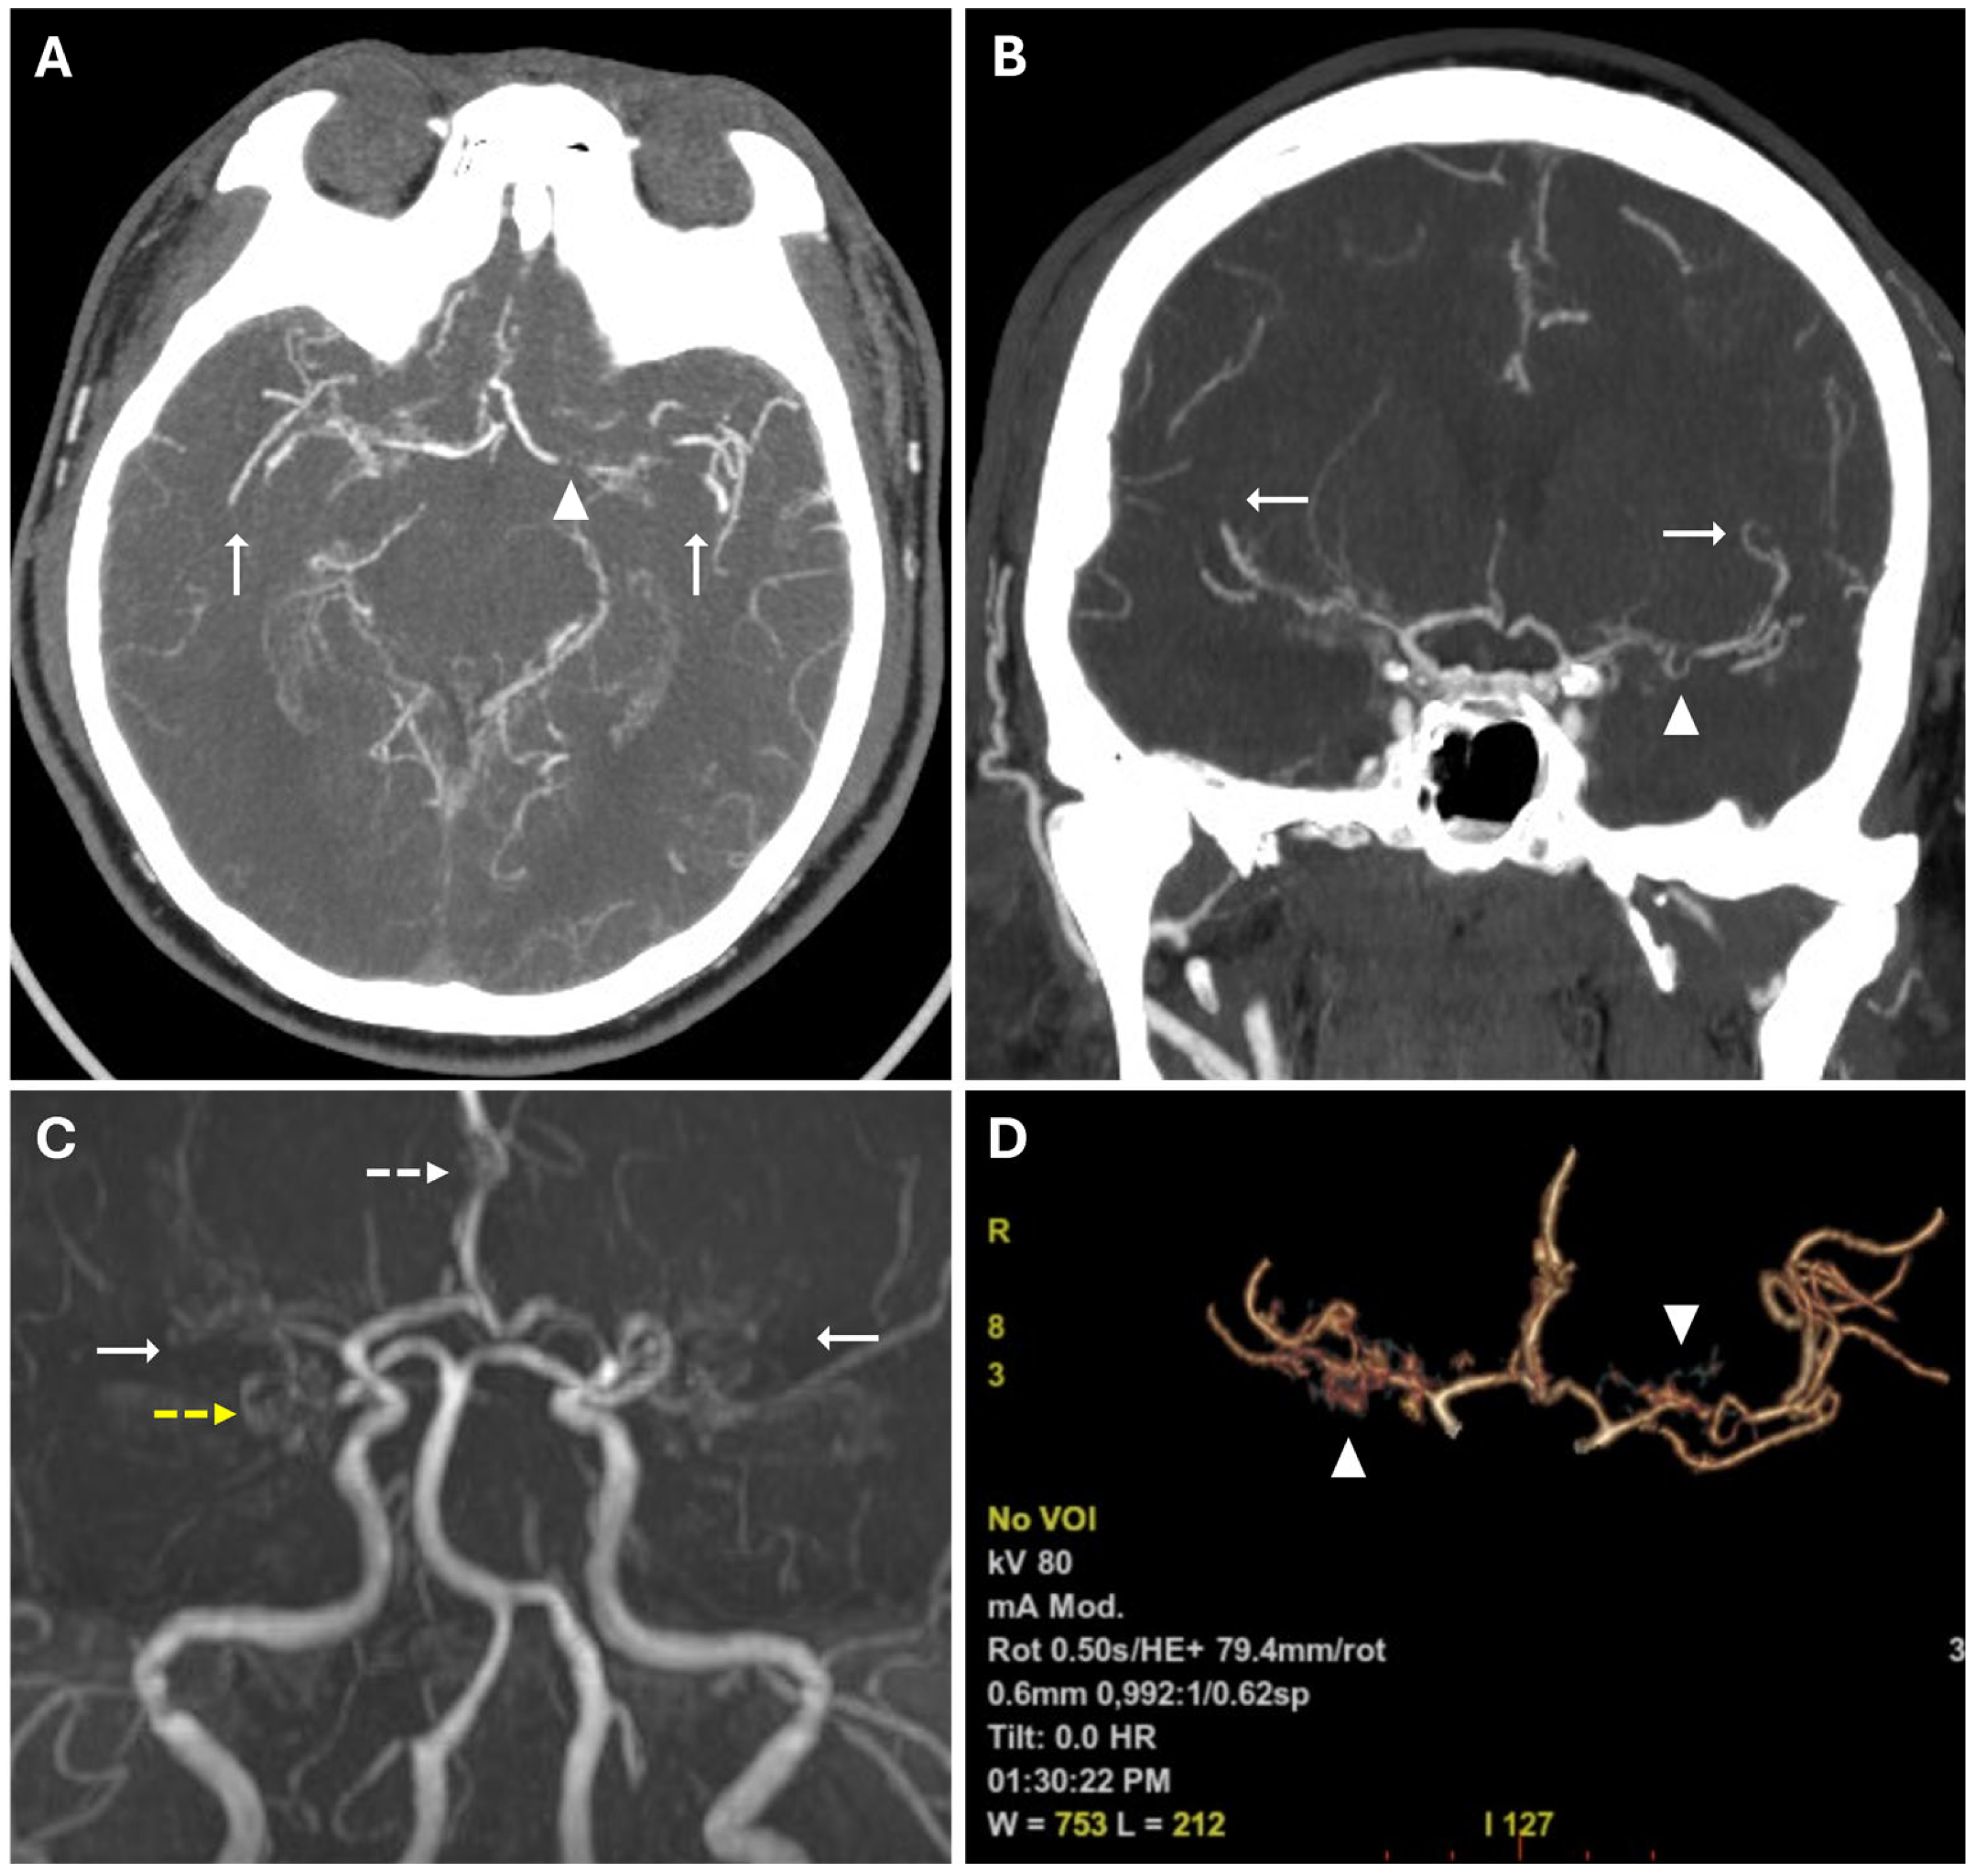

Prominent leptomeningeal collaterals with slow flow, resulting in high signal intensity on FLAIR sequences, were detected in the subarachnoid spaces of the left hemisphere (“ivy sign”) (Figure 4).

Figure 4. The Ivy sign in the left-brain hemisphere. (A) Axial 2D FLAIR sequence shows linear hyperintensity along the cortical sulci of the left hemisphere (white arrowheads); note a subacute ischemic lesion in the right parietal lobe (white arrow). (B) CTA Maximal Intensity Projection (MIP) shows prominent leptomeningeal collaterals in the left hemisphere, with abnormal enhancement of blood vessels, “ivy-like” (white arrowheads); the absence of opacification of distal branches of the right MCA (white arrow) was consistent with recent ischemic stroke in the right parietal lobe vascular territory.

The “ivy” sign is an indicator of slow or retrograde flow in engorged pial vessels, via leptomeningeal collaterals, and is characterized by linear hyperintensity on FLAIR sequences in cerebral sulci of the affected brain region, as in the case we report. The ivy sign is also detected on contrast-enhanced T1-weighted sequences, and it may be less pronounced on 3D FLAIR compared to 2D FLAIR sequences, probably because of the differential impact of flow velocity in the 2D versus 3D FLAIR imaging; it has also been hypothesized that the uniform suppression of the cerebrospinal fluid signal inherent to 3D FLAIR may obscure both the abnormal thickening and/or signal intensity of the leptomeninges, as well as pathological signal alterations within the CSF itself [18,19]. In the case we report, this sign was more evident in the brain hemisphere opposite to the ischemic lesion. This apparent paradox could be explained by the rapid onset of arterial occlusion in the right middle cerebral artery that did not allow the development of compensatory collaterals [20]. The ivy sign has been associated with cerebrovascular reactivity and decreased vascular reserve, and, following revascularization surgery, it can improve or worsen temporarily due to hyperperfusion [14]. Moreover, an elevated Suzuki stage (≥3), CBF reduction, and high risk of severe ischemic events, correlate independently with the ivy sign [21].